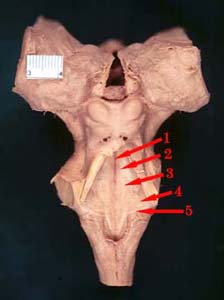

EXTERNAL MORPHOLOGY OF THE BRAIN STEM

FLOOR OF 4

th

VENTRICLE

1. Median sulcus

2. Median eminence

3. Facial colliculus

4. Vestibular area

5. Striae medullares